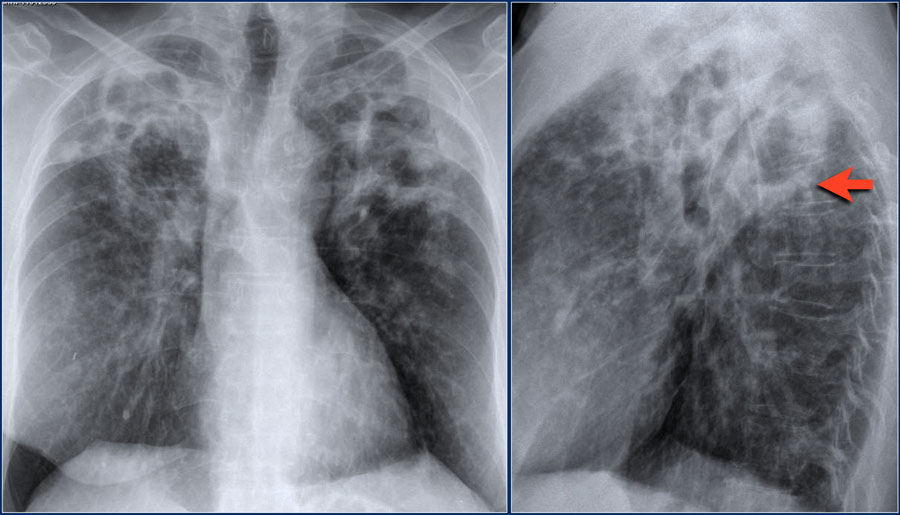

Рентгеновские снимки при врожденной эмфиземе легкого

Раздел: Визуальные уроки